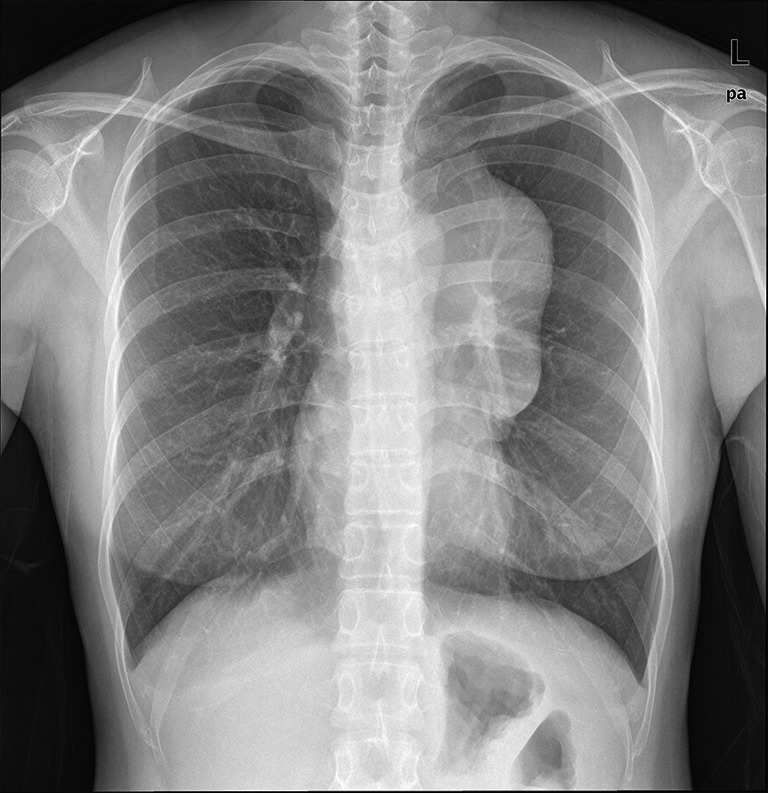

Figure 1.

Chest radiograph (postero-anterior view) shows a large mediastinal mass occupying the left side without deviation or compression of the distal trachea, carina, or main bronchi.